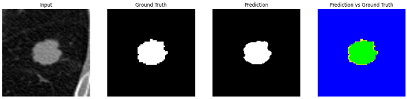

3.4.2. Representative Cases with Segmentation Challenges on the MEF-PN35 Dataset

To complement the quantitative evaluation, we present a set of representative cases from the clinical dataset that exhibited typical segmentation challenges. These cases were selected to reflect diverse morphological characteristics observed in pulmonary nodules, such as spiculated boundaries, small size, vessel adherence, pleural attachment, cavitation, and clear isolation. Rather than aiming for exhaustive categorization, our intent is to highlight a range of practical difficulties encountered in real-world scenarios and to qualitatively assess how different boundary-aware loss functions respond to these variations. Each challenge is labeled (C1) through (C5) in Table 10 and is consistently referenced in the corresponding detailed illustrations that follow.

Following the summary in Table 11, we present detailed visual comparisons for selected representative cases, each corresponding to a specific segmentation challenge. These cases are consistently labeled using the Challenge ID (CID) codes defined in Table 9 to facilitate cross-referencing between the summary and the case illustrations. Each table reports segmentation results across three loss configurations (Sobel, Laplacian, and Hausdorff) using five columns. Loss indicates the boundary loss formulation applied in each case, where Dice loss is combined with a boundary term computed using Sobel, Laplacian, or Hausdorff operators. The Segmentation Result column shows four images side by side: the input CT patch, the manual ground truth, the model prediction, and a color-coded difference map between ground truth and prediction. In this map, green indicates true positives, blue represents true negatives, red corresponds to false positives, and yellow denotes false negatives. The final column, Attention Map, presents Grad-CAM visualizations derived from one of the Adaptive Attention Fusion (AAF) layers in the encoder path. These maps illustrate the spatial focus of the model, with red/yellow regions indicating strong attention and lighter or neutral tones indicating lower activation. All six cases are presented in detail in Table 11, Table 12 and Table 13, providing a comprehensive qualitative analysis of how each loss configuration performs under specific segmentation challenges observed in real clinical data.